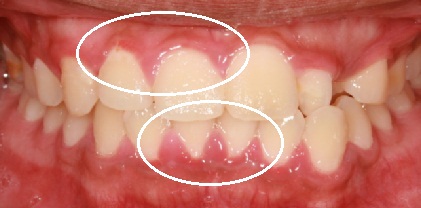

Forman parte del sistema de soporte de los dientes en los maxilares. Si la encía está sana, los dientes están perfectamente fijados, lo que garantiza una buena masticación y aíslan del organismo de agresiones del medio externo a través de la boca. La encía es un contribuyente del apoyo junto al hueso alveolar, y ligamento periodontal. El ligamento periodontal y el hueso alveolar insertan el diente en el organismo, y la encía es la barrera que protege el mismo de las agresiones tanto físicas como químicas, y bacterianas, que nos vienen del exterior.

La causa más frecuente de las encías inflamadas son las bacterias, en la boca existen más de trescientos tipos diferentes, muchas de ellas son potencialmente agresivas para el soporte. Las bacterias que habitan en la boca se esparcen sobre la superficie de los dientes, especialmente en el surco gingival, provocando la placa bacteriana. Cuando las bacterias crecen sobrepasando un cierto nivel, son capaces de producir lesiones en los tejidos periodontales. La gravedad de estas lesiones depende de la susceptibilidad individual que es una característica genéticamente determinada.

El elemento fundamental para sufrir enfermedad periodontal, es la predisposición individual, y ésta viene condicionada genéticamente. Es un error pensar que sólo la predisposición genética es suficiente para sufrir periodontitis, se necesita la presencia de bacterias. Con frecuencia las personas que padecen periodontitis, sobre todo aquellas que manifiestan más severas, se encuentran afectados entre padres y / o hermanos, lo que nos diría que es de carácter familiar o hereditario. Por tanto, y considerando que hoy por hoy, poco podemos hacer para variar la predisposición genética, la forma de prevenir y tratar las periodontitis es el control de la placa bacteriana.